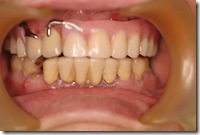

患者A先生

上顎 正面 下顎

患者B小姐

以上兩位患者口內狀況非常複雜,要制定一個好的治療計畫,

不只要考慮到患者的牙齒條件,

還要顧及患者意願、時間、金錢、評估可獲得的結果等等。

所以像這類型的Case 醫師通常在初步的溝通後會先做出一兩個不同的治療計畫,

再和患者解釋,了解患者接受程度。